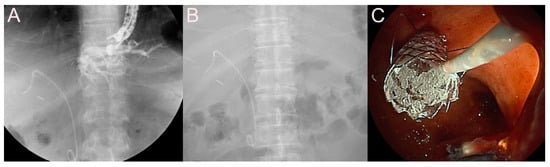

2.4. Stent for EUS-Guided Pancreatic Duct (PD) Drainage

2.4.1. Use of the Plastic Stent

2.4.2. Use of the SEMS

2.5. Stent for EUS-Guided Creation of Entero-Enteric Anastomosis